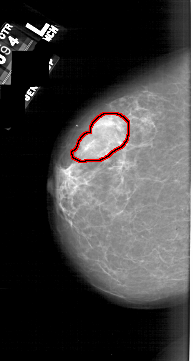

A_1740_1.LEFT_CC

LEFT_CC LINES 6136 PIXELS_PER_LINE 3271 BITS_PER_PIXEL 12 RESOLUTION 43.5 OVERLAY

FILE: A_1740_1.LEFT_CC.OVERLAY

TOTAL_ABNORMALITIES 1

ABNORMALITY 1

LESION_TYPE CALCIFICATION TYPE PLEOMORPHIC DISTRIBUTION CLUSTERED

ASSESSMENT 4

SUBTLETY 5

PATHOLOGY BENIGN_WITHOUT_CALLBACK

TOTAL_OUTLINES 1

BOUNDARY